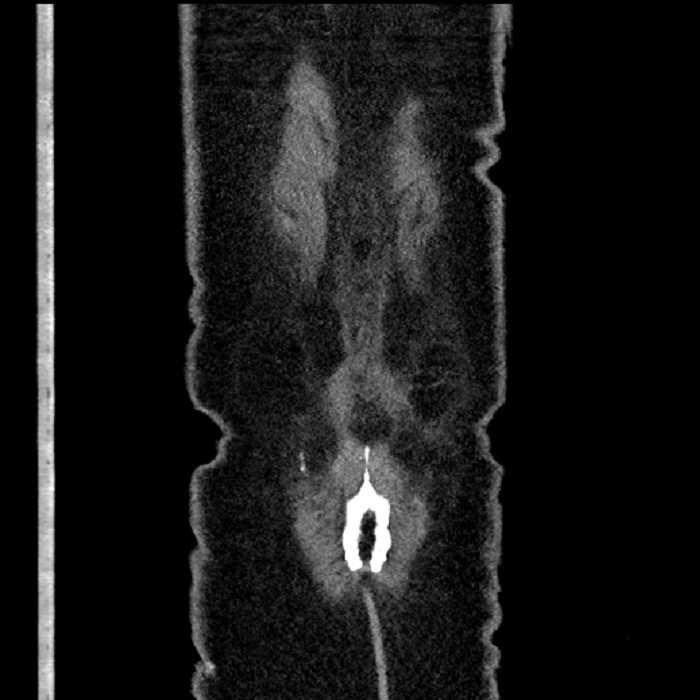

• The classic CT imaging appearance is a double target sign with internal low density surrounded by an internal enhancing rim (capsule) and a low density external rim (edema)

Hepatic abscess showing the double target sign with low density internally surrounded by a thin inner enhancing rim (red arrow) and ill-defined outer low density rim (yellow arrow). Blue arrow indicates an internal septation. Red arrows: additional smaller subcapsular abscesses. Red arrow: focal contained perforation associated with diverticulitis.